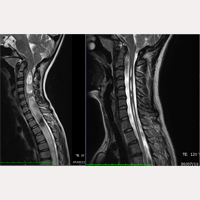

Olá! Sou a mãe de uma menina que foi operada aos 8 anos de idade mediante a secção do filum terminale em dezembro de 2013. Ela foi a quarta paciente japonesa operada pelo Institut Chiari de Barcelona. A nossa filha padece da Malformação de Arnold Chiari I, Siringomielia e Escoliose idiopáticas. Já se passaram 6 anos e meio desde que ela foi operada e tudo tem transcorrido muito bem. A nossa filha tinha uma Siringomielia muito grave, cuja cavidade chegava até a região lombar. No entanto, depois de 6 meses da cirurgia, a cavidade diminuiu para a metade e, após 18 meses, a sua extensão passou a ser de um terço do que era antes da cirurgia. A cavidade ainda persiste, mas está diminuindo aos poucos. Depois de 2 anos e meio, também foi observada uma mudança na descida das amígdalas cerebelares e, após 4 anos e meio, ela teve ainda mais melhorias. O médico da nossa filha no Japão se surpreende com o resultado da secção do filum terminale, e nos diz que, como a cavidade da Siringomielia diminuiu tanto, ela não terá problemas se não apresentar sintomas. No entanto, como não se pode evitar completamente o avanço da escoliose, o Institut nos recomendou o método Schroth e, após 4 meses da cirurgia, a nossa filha começou a praticá-lo. Durante 4 anos, pudemos frear a progressão da escoliose, mas quando a nossa filha entrou no período de crescimento, em dezembro de 2018, a curvatura da escoliose piorou, chegando a 48 graus. Por isso, decidimos mudar de centro de reabilitação, e depois de 1 mês, a curvatura diminuiu para 33 graus e, assim, seguimos as indicações para melhorar a escoliose dela.